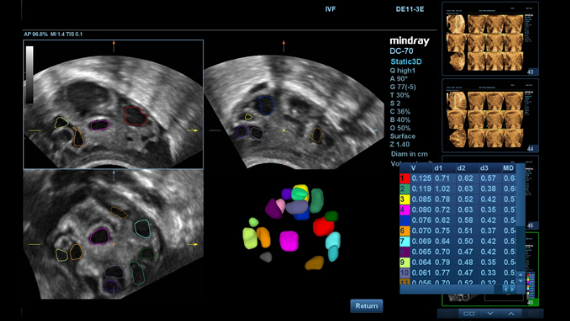

ImĂĄgenes clĂnicas